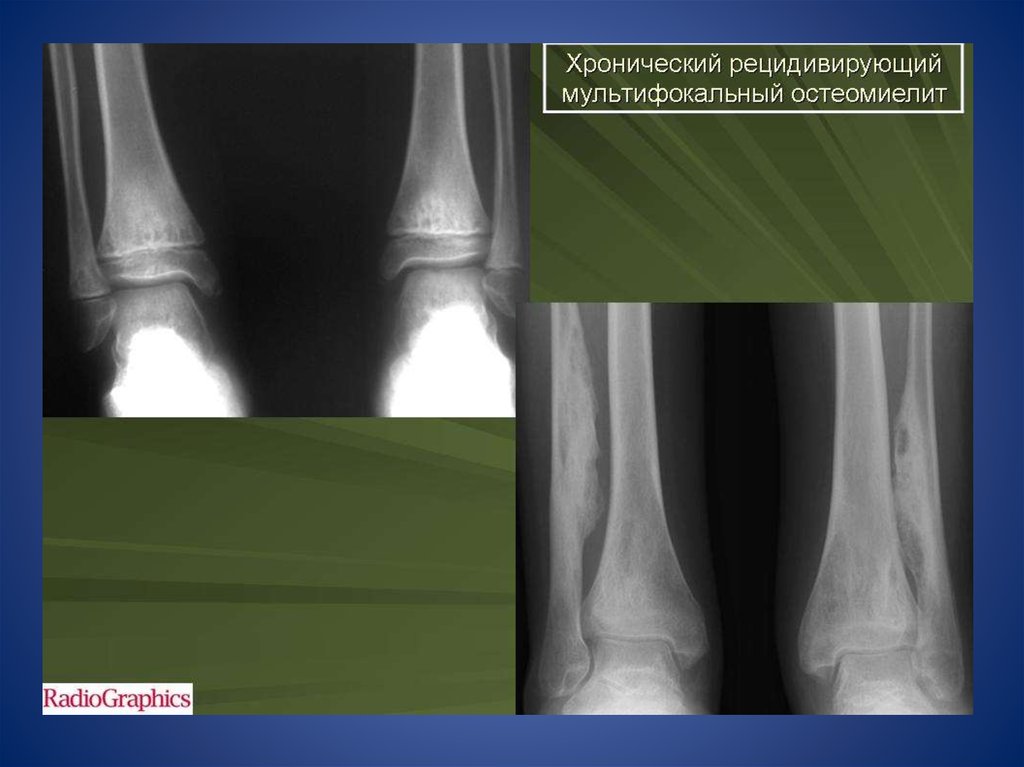

Хронический рецидивирующий

мультифокальный остеомиелит

В случае, если хроническое течение

остеомиелита протекает длительно,

трубчатая кость начинает перестраиваться в

губчатую, на рентгене это выражается

следующими признаками:

1Костномозговой канал полностью или

частично замещается губчатым веществом

кости.

2Надкостница становится заметно тоньше.

3На рентгене появляются дополнительные

участки просветления.